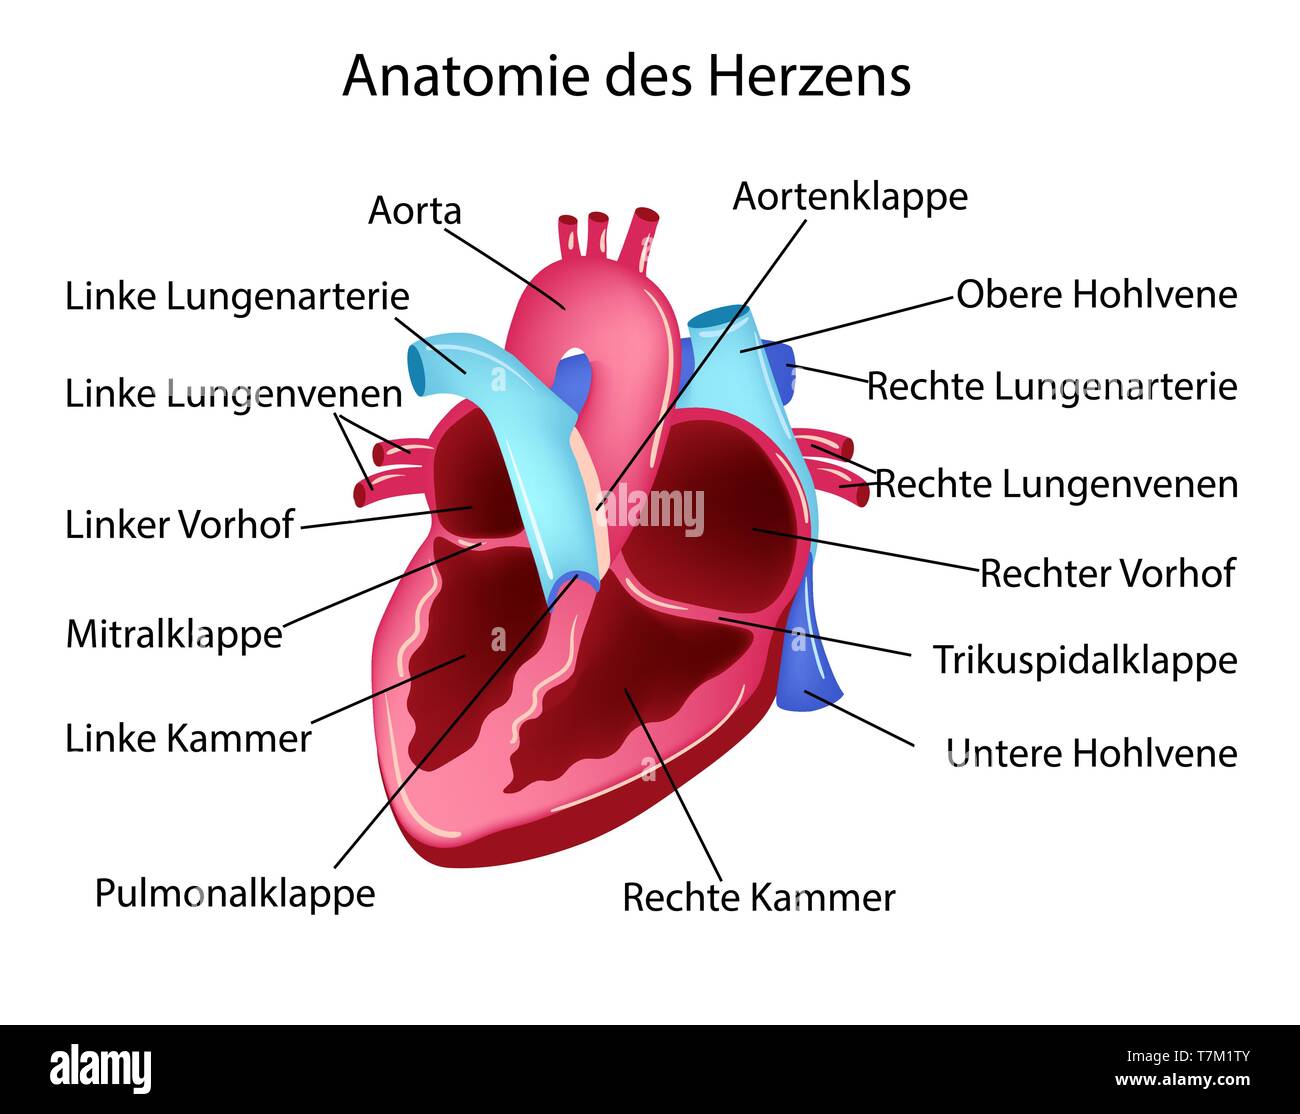

Vector illustration in german language with medical structure of heart Stock Vectorhttps://www.alamy.com/image-license-details/?v=1https://www.alamy.com/vector-illustration-in-german-language-with-medical-structure-of-heart-image245688267.html

Vector illustration in german language with medical structure of heart Stock Vectorhttps://www.alamy.com/image-license-details/?v=1https://www.alamy.com/vector-illustration-in-german-language-with-medical-structure-of-heart-image245688267.htmlRFT7M1TY–Vector illustration in german language with medical structure of heart